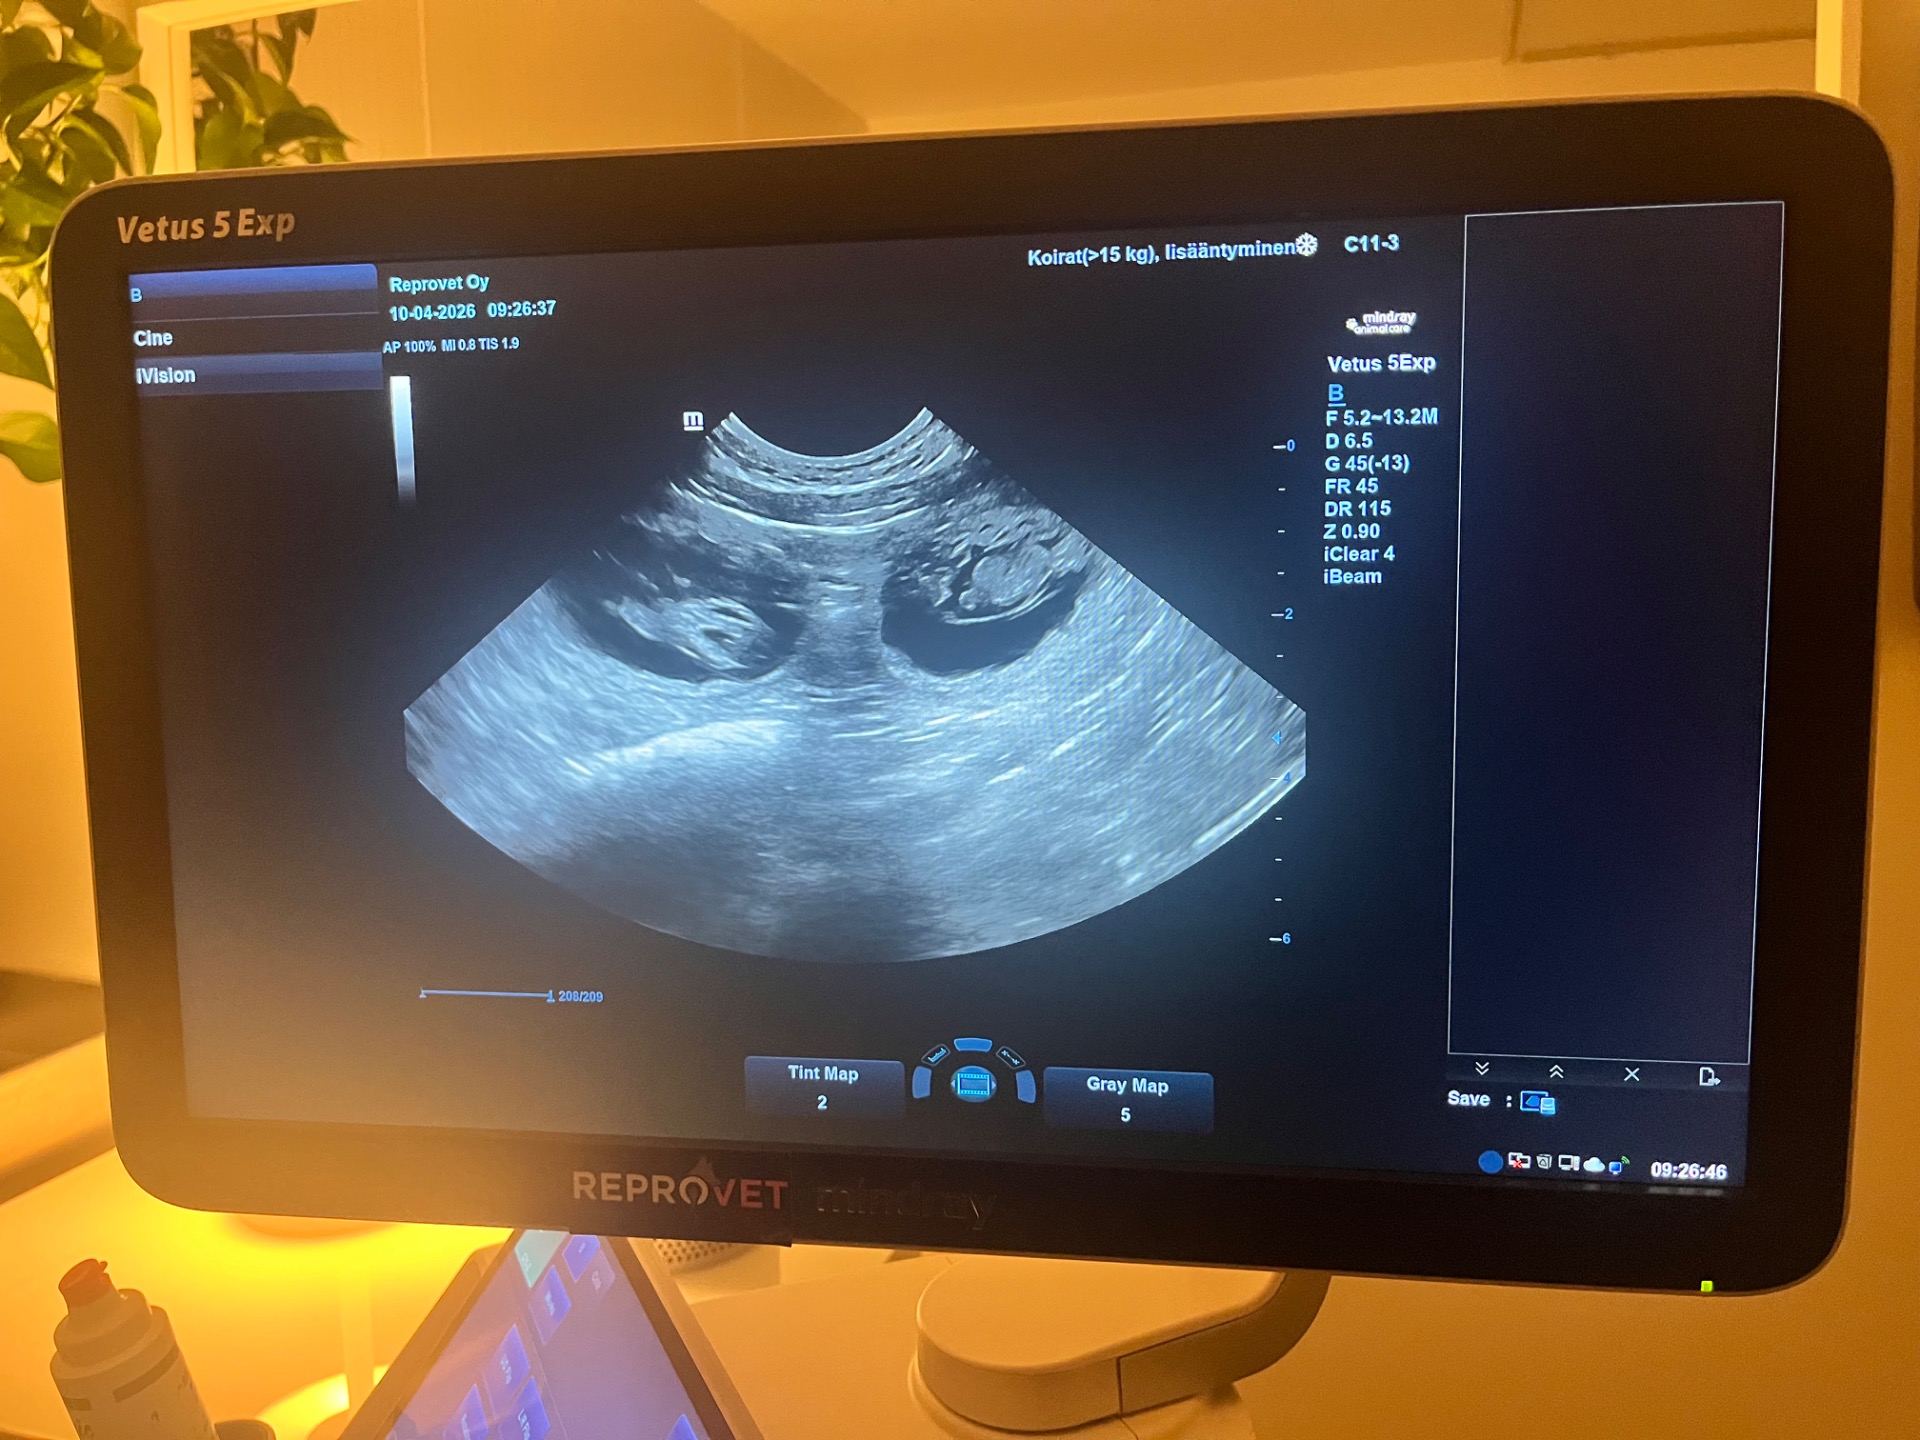

Meiran (Trusted Companion Alina) tiineys varmistui tänään tiineysultrassa, jossa näkyi 8 pikkuista nahkavauvaa. Pennut syntyvät arviolta 12.5.2026. Pentujen isä on Dazzly (Millake’s Dazzling Broderick).

10.4.2026 tiineysultra Reprovet Oy:ssä.